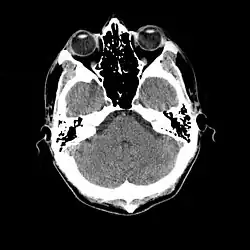

Tomografia computadorizada (português brasileiro) ou tomografia computorizada (português europeu) (TC), originalmente apelidada tomografia axial computadorizada / computorizada (TAC) - em inglês: X-ray computed tomography - é um exame complementar de diagnóstico por imagem, que consiste numa imagem que representa uma secção ou "fatia" do corpo. É obtida através do processamento por computador de informação recolhida após expor o corpo a uma sucessão de raios X. Seu método principal é estudar a atenuação de um feixe de raios X durante seu trajeto através de um segmento do corpo, no entanto, ela se distingue da radiologia convencional por diversos elementos.[1]

A TC baseia-se nos mesmos princípios que a tomografia convencional, segundo os quais tecidos com diferentes composições absorvem a radiação X de forma diferente. Ao serem atravessados por raios X, tecidos mais densos (como o fígado) ou com elementos mais pesados (como o cálcio presente nos ossos), absorvem mais radiação que tecidos menos densos (como o pulmão, que está cheio de ar).[1][3]

Assim, uma TC indica a quantidade de radiação absorvida por cada parte do corpo analisada (radiodensidade), e traduz essas variações numa escala de cinzentos, produzindo uma imagem. Cada pixel da imagem corresponde à média da absorção dos tecidos nessa zona, expresso em unidades de Hounsfield, em homenagem ao criador da primeira máquina de TC.

Características das imagens tomográficas

Entre as características das imagens tomográficas destacam-se os pixeis, a matriz, o campo de visão (ou fov, em inglês: field of view), a escala de cinza e as janelas.[1]

Em relação às imagens, existe uma convenção para traduzir os valores de voltagem detectados em unidades digitais. Dessa forma, temos valores que variam de –1000, onde nenhuma voltagem é detectada: o objeto não absorveu praticamente nenhum dos fótons de raio-X, e se comporta como o ar; ou um valor muito alto, algo como +1000 ou mais, caso poucos fótons cheguem ao detector: o objeto absorveu quase todos os fótons de raio-X. Essa escala onde –1000 é mais escuro, 0 é um cinza médio e +1000 (ou mais) é bem claro. Dessa forma quanto mais raio-X o objeto absorver, mais claro ele é na imagem. Outra vantagem é que esses valores são ajustados de acordo com os tecidos biológicos.

A escala de cinza é formada por um grande espectro de representações de tonalidades entre branco, cinza e o preto. A escala de cinzas é que é responsável pelo brilho de imagem. Uma escala de cinzas foi criada especialmente para a tomografia computadorizada e sua unidade foi chamada de unidade Hounsfield , em homenagem ao cientista que desenvolveu a tomografia computadorizada. Nesta escala temos o seguinte:

- zero unidades Housfield (0 HU) é a água,

- ar -1000 (HU);

- osso de 700 HU(osso esponjoso) a 3000 HU(osso denso);

- gordura de –100 a -50 HU;

- músculo de 10 a 40 HU

As imagens tomográficas podem ser obtidas em dois planos básicos: o plano axial (perpendicular ao maior eixo do corpo) e o plano coronal (paralelo a sutura coronal do crânio ou seja é uma visão frontal). Após obtidas as imagens, recursos computacionais podem permitir reconstruções no plano sagital (paralelo a sutura sagital do crânio) ou reconstruções tridimensionais.